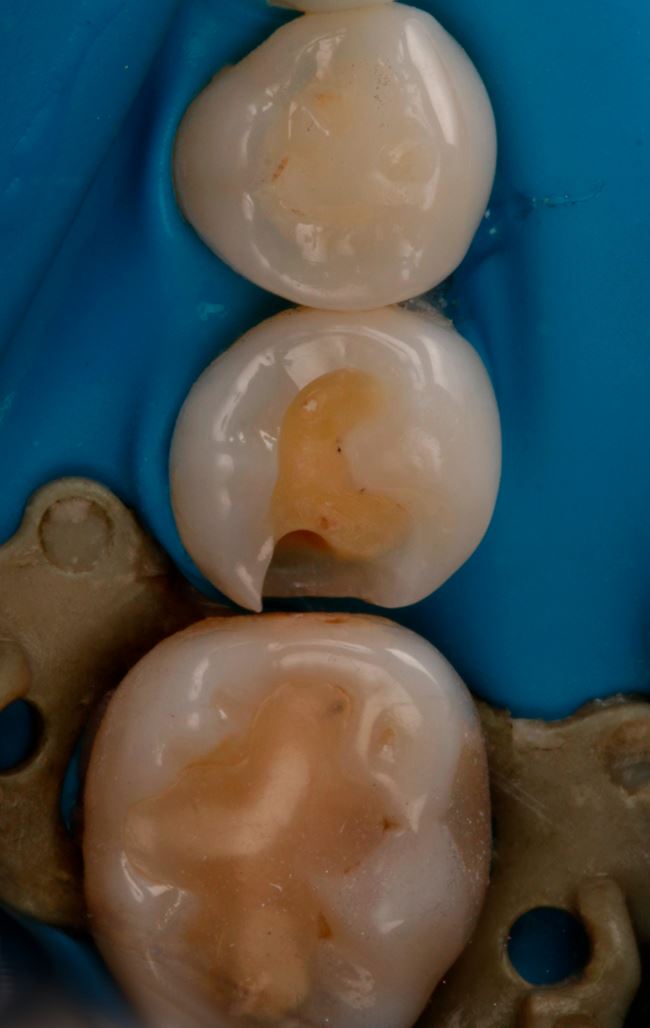

Ubytek na powierzchni dystalnej okazuje się całkiem duży, obejmuje znaczną część zębiny. Teraz nie ma już wątpliwości, że bez wypełnienia się nie obejdzie, a więc podajemy znieczulenie, zakładamy koferdam (ryc. 7) i przystępujemy do opracowania. Po usunięciu amalgamatu w dystalnej części ubytku widać ciemniejszą zębinę (ryc. 8). Usuwamy dystalną listewkę szkliwa i już widać wyraźne odwapnienie (ryc. 9). Dalej jest tylko ciemniej i głębiej (ryc. 10 i 11).

Ryc. 7. Ząb 45 przed usunięciem wypełnienia amalgamatowego.

Ryc. 8. Ząb 45 po usunięciu wypełnienia amalgamatowego.

Ryc. 9. Ząb 45 po częściowym otwarciu ubytku.

Ryc. 10. Ząb 45 z częściowo opracowanym ubytkiem próchnicowym kl. II D.

Ryc. 11. Ząb 45 po opracowaniu ubytku kl. II D.